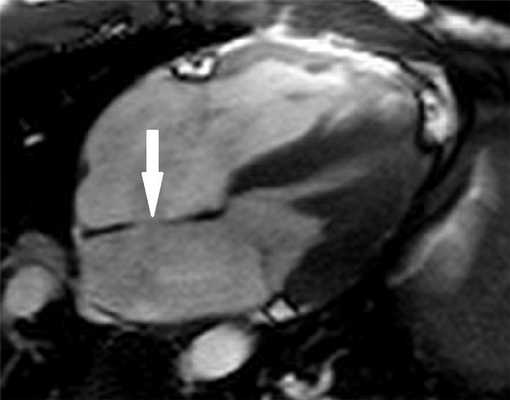

Рисунок 1. МРТ. Четырехкамерное сечение сердца. Стрелкой указан дефект межпредсердной перегородки (ДМПП).